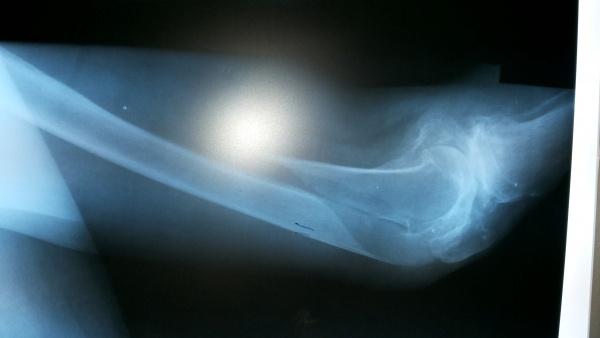

辅助检查:X片示:左股骨远端螺旋形骨折,胸片、骨盆未见外伤性改变,左膝关节退行性改变

诊疗过程:入院给予:屈膝位胫骨结节持续骨牵引,消肿止痛,完善相关检查。今日复查床旁X片后家属要求手术。

入院时侧位

牵引后床旁侧位片